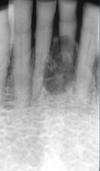

What is this radiographic finding?

Periapical Cysts

►Would need to test both teeth for vitality.

What is this radiographic finding?

Periapical Cyst

What are these radiographic findings?

Residual Cysts

What is the radiographic finding?

Residual Cyst